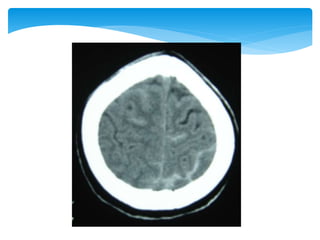

 Appearance of the normal structures

CT Scan

 Appearance ofthe normal structures CT Scan